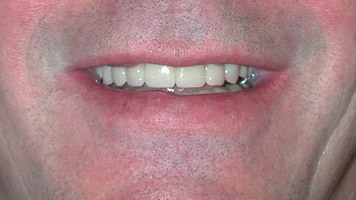

Vue satisfaisante du sourire du patient.